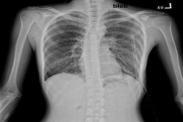

老年人厭氧菌性肺炎癥狀

• 老年人厭氧菌性肺炎

628健康網(wǎng)為您分享有關老年人厭氧菌性肺炎的癥狀,老年人厭氧菌性肺炎的治療方法,老年人厭氧菌性肺炎的預防知識,老年人厭...